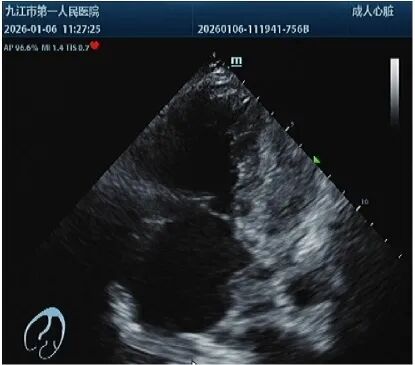

经床边超声、心电图等检查,医生快速确诊:患者急性右心扩大、肺动脉高压,双下肢静脉有血栓,且左股静脉有血栓游动,另有典型的SⅠQⅢTⅢ心电图改变,结合患者低血压,诊断为高危急性肺动脉栓塞。进一步肺动脉PTCA检查显示患者双肺多处肺动脉分支被血栓阻塞,死亡风险极高。